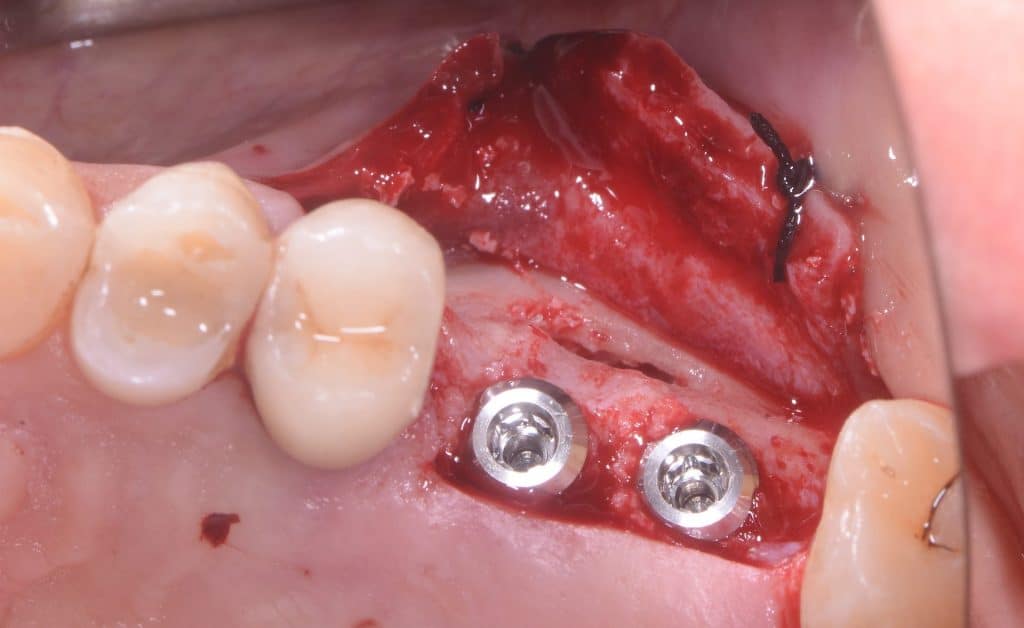

- Two implants are placed drilling the 3 mm of residual crestal bone

- To drill the holes it is recommended to use vibrating burs mounted on a sonic handpiece

- You can see the apexes of the depth indicators inside the maxillary sinus

- Two 8 mm Straumann TLX implants placed

- Implants can be seen inside the maxillary sinus through the bone window

Depth indicators

lateral sinus wall, implants view

lateral sinus window view